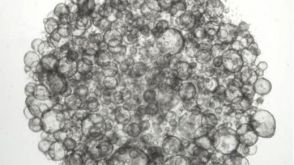

研究综述The Predictive Power of Organoid-Based New Approach Methodologies in Drug Discovery细胞类型:

上皮细胞,多能干细胞,肠道细胞,胰腺细胞,肾脏细胞,PSC衍生上皮细胞,PSC衍生肝细胞,呼吸道细胞